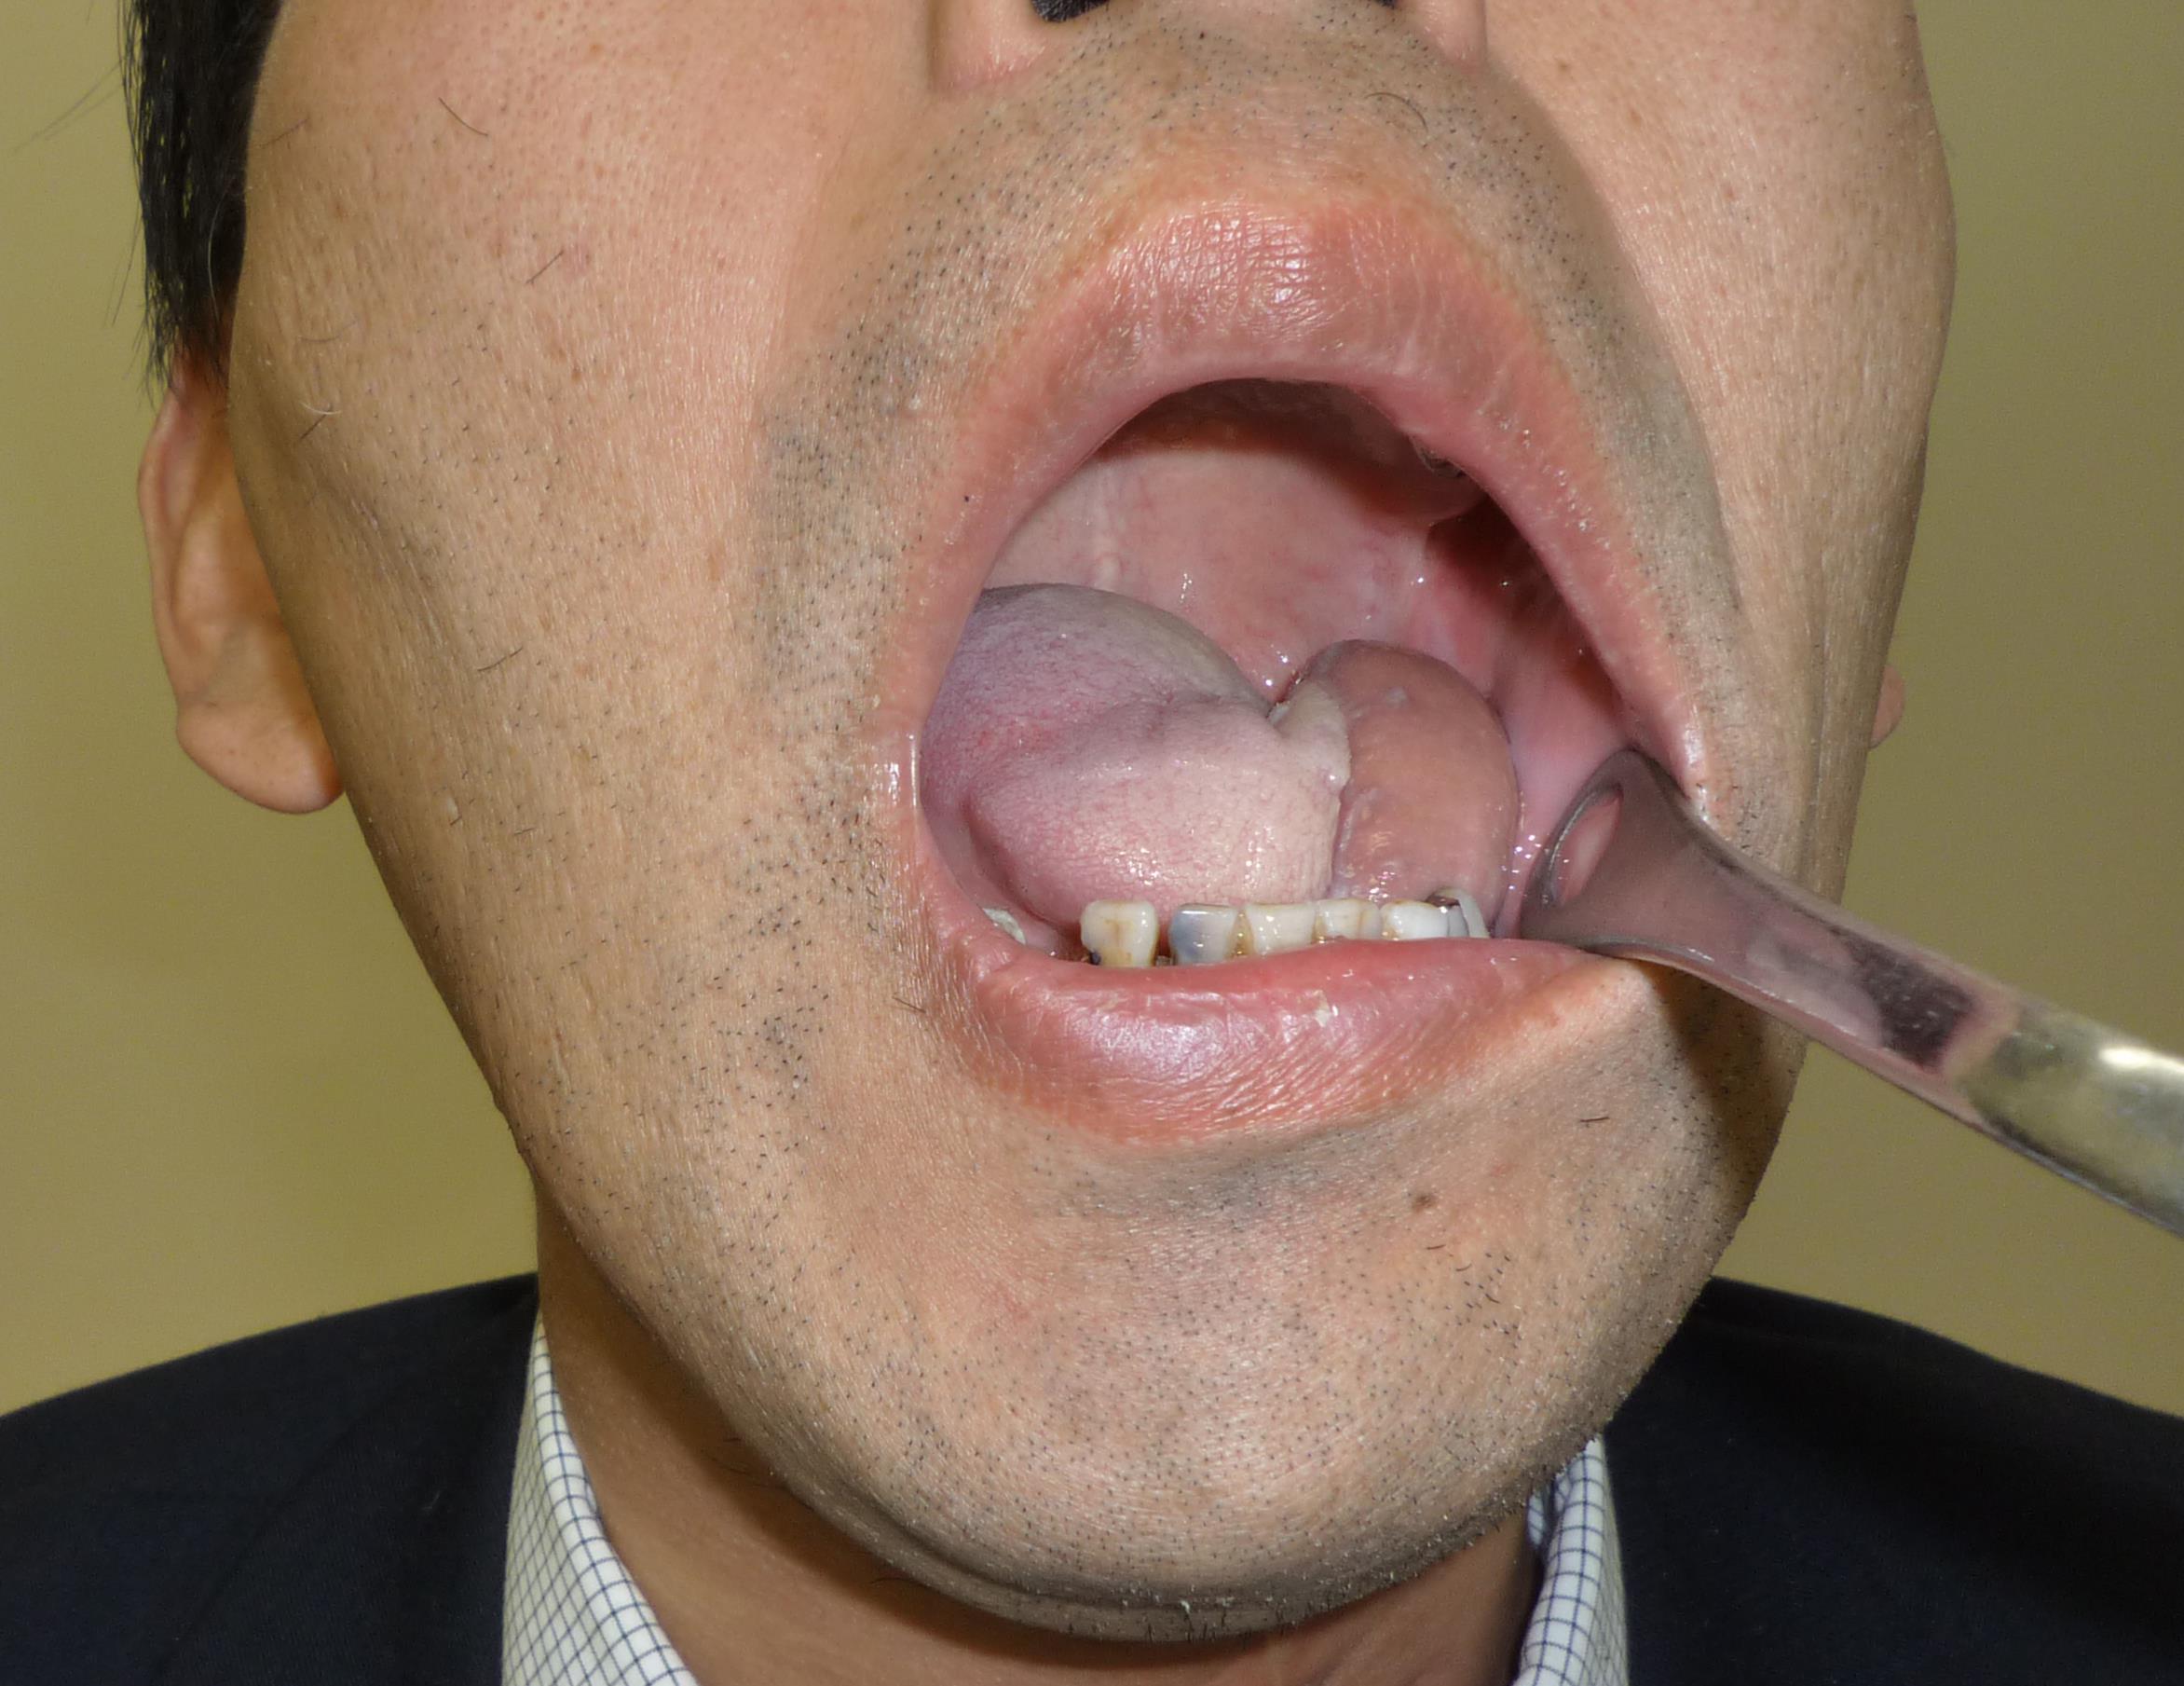

なんかできものができた 中咽頭癌 そして味覚を失った まさぱく